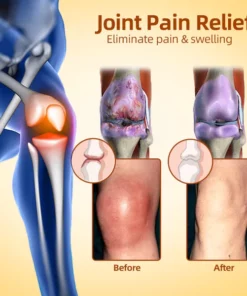

- Relieve Arthritis Pain

- Eliminate joint inflammation

- Eliminates cysts and edema